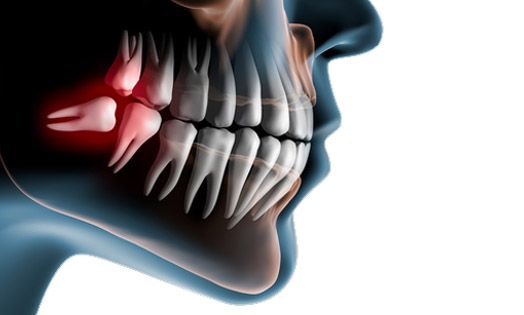

El nombre científico de las conocidas muelas del juicio es muelas cordales o terceros molares, se trata de las últimas piezas definitivas en erupcionar.

En aquellos casos en que las muelas del juicio no tienen espacio suficiente en la cavidad bucal, ello puede provocar malposiciones y apiñamiento dental. Aunque no salen a todo el mundo, las muelas del juicio son en total 4: 2 en el maxilar superior y 2 en la mandíbula.

Debemos tener presente que no todas las muelas del juicio retenidas dan señales claras de su presencia. Probablemente al principio no notaras ningún problema; sin embargo, a medida que la muela del juicio siga su curso y comience a crecer, es posible que se presenten síntomas de la muela retenida como los que describimos a continuación en Centro Dental Guillermo López:

El dolor es la primera pista que nos indica que algo no va del todo bien en nuestra boca Podrías notarlo en la mandíbula, justo detrás de las últimas muelas, o incluso irradiándose hacia otras áreas de la cabeza.

2.2) Hinchazón y enrojecimiento

Según la muela del juicio retenida vaya ejerciendo presión, es posible que la encía se inflame y adquiera un tono más rojizo. Además, podrías notar que la zona se vuelve más sensible al tacto.

En ciertos casos las muelas de juicio pueden estar incluidas, es decir totalmente cubiertas por la encía y esto puede generar infección o un quiste y puede dañar las raíces de otro molar.

En otras ocasiones están parcialmente erupcionadas y eso suele generar episodios de infecciones y problemas periodontales por el acúmulo de bacterias. Cuando tienen caries salvo situaciones concretas no se suelen realizar empastes y se prescribe también la extracción.